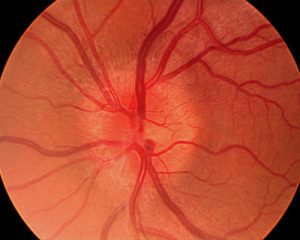

Optical coherence tomography (OCT) enables the measurement of retinal nerve fiber layer (RNFL) thickness and retinal ganglion cell layer integrity. In geriatric patients, it is crucial to separate the normal age-related RNFL thinning from that caused by optic neuritis (ON) during the initial assessment. OCT performed repeatedly over a period can be a very useful way to observe the damage of the optic nerve over time and also to assess how effective the treatments are.